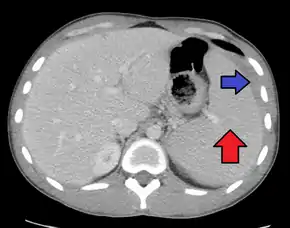

Spleen enlargement is common in the second and third weeks, although this may not be apparent on physical examination. Rarely the spleen may rupture.[24] There may also be some enlargement of the liver.[22] Jaundice occurs only occasionally.[14][25]

Splenomegaly is a common symptom of infectious mononucleosis and health care providers may consider using abdominal ultrasonography to get insight into the enlargement of a person's spleen.[57] However, because spleen size varies greatly, ultrasonography is not a valid technique for assessing spleen enlargement and should not be used in typical circumstances or to make routine decisions about fitness for playing sports.[57]